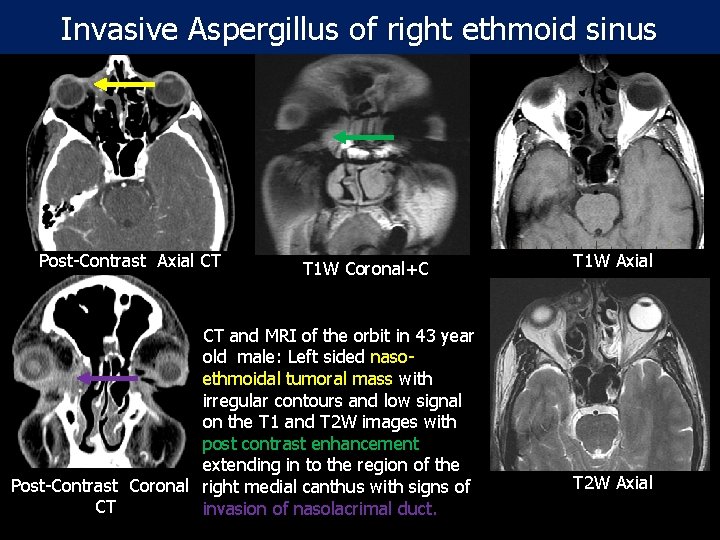

Invasive Aspergillus of right ethmoid sinus Post-Contrast Axial CT T 1 W Coronal+C CT and MRI of the orbit in 43 year old male: Left sided nasoethmoidal tumoral mass with irregular contours and low signal on the T 1 and T 2 W images with post contrast enhancement extending in to the region of the Post-Contrast Coronal right medial canthus with signs of CT invasion of nasolacrimal duct. T 1 W Axial T 2 W Axial